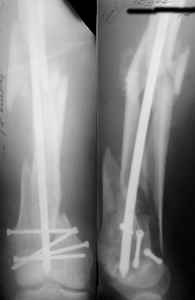

I presented a series of ~25 such cases at EuroTrauma'2004. Many cases were discussed here. I attach am example. Look also recent cases at http://www.hwbf.org/hwb/conf/alex58/scfx.htm,

http://www.hwbf.org/hwb/conf/alex63/alex63.htm

I do realize that you are master surgeon, and congratulations on another excellent, spectacular case (result), but,

- Your last posted case: how is possible to have secure fixation with applied construct without additional casting, bracing or Ilizarov?

At that moment we had in stock only the 10 mm solid nails so of course there was no idea about early weight bearing. But it was quite enough for early knee ROM excersises (see attached). Two locking screws through the distal block provided that.